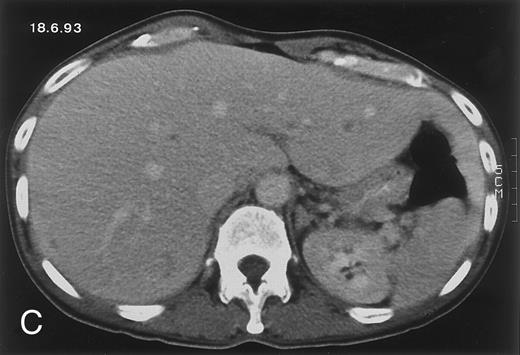

Radiologic evolution in patient A. (A) Postcontrast abdominal CT scan on March 16, 1993 shows multiple small hypodense areas in all segments of the liver, suggestive of hepatic candidiasis. Seven days previously, the patient had recovered from severe neutropenia after the first cycle of chemotherapy for AML. (B) On April 23, 6 days after the neutrophil count had dropped below 500/μL in the second cycle of chemotherapy, there is no evidence of focal lesions on postcontrast CT scan. (C) On June 18, when neutrophils were normalized for 46 days, CT scan again shows multiple small abscesses.

Evolution of fungal lesions on CT scans during and after neutropenia is summarized in Table 2. Figure 1 (patient A) and Fig 2 (patient B) serve to illustrate Table 2.

In three patients, multiple round lesions were seen on postcontrast CT scans of the abdomen in the liver and the spleen, while in two cases, lesions could only be seen in the liver (Table 2). Following the diagnosis of disseminated candidiasis, these lesions decreased in size and visibility during subsequent neutropenia in three patients (compare Fig 2A and B) and disappeared completely in two patients (compare Fig 1A and B). The numbers of days of severe neutropenia (neutrophils <500/μL) at the time the CT scan was performed are listed in Table 2. After recovery from neutropenia and despite continued antifungal therapy, the size and visibility of the lesions increased again (Fig 1C). Similarly, the number of days since recovery from severe neutropenia (neutrophils >500/μL) are listed in Table 2. In two of three patients treated with another cycle of myeloablative chemotherapy, this waxing and waning pattern of radiologic lesions could be seen again (Fig 1D and E). In all patients, lesions eventually disappeared (Figs 1F and 2D) after prolonged antifungal therapy.